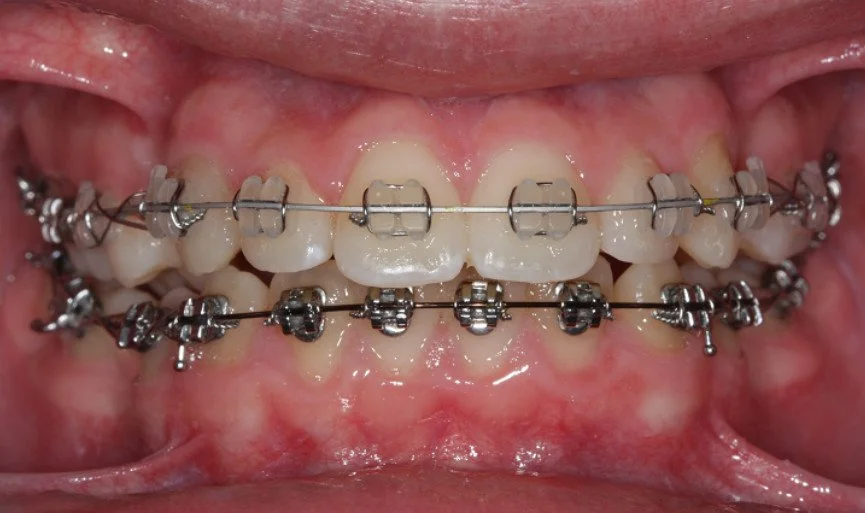

CASO ESTRATTIVO

In alcuni casi, per allineare correttamente i denti senza creare problemi come recessioni gengivali o danni all’osso di supporto, è necessario ricorrere a estrazioni strategiche. Questo accade quando lo spazio in arcata è insufficiente per accogliere tutti i denti in una posizione stabile e armoniosa. Estrarre alcuni elementi dentari permette di ottenere un risultato estetico e funzionale migliore, garantendo una masticazione corretta e preservando la salute dei tessuti gengivali e ossei.

BEFORE

DURING

Trattamento con 4 estrazioni di una malocclusione di classe II con proclinazione degli incisivi superiori e inferiori.